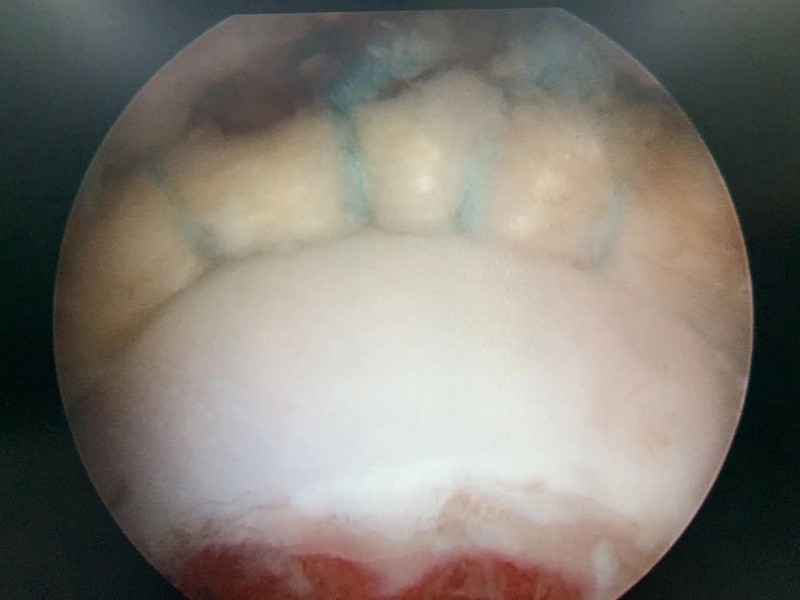

病例,王X,女,32岁,反复活动后髋关节疼痛6月余,休息能缓解,诊断为髋关节撞击综合征合并盂唇损伤,规律保守治疗后无效,行髋关节镜下手术。

图12 术中